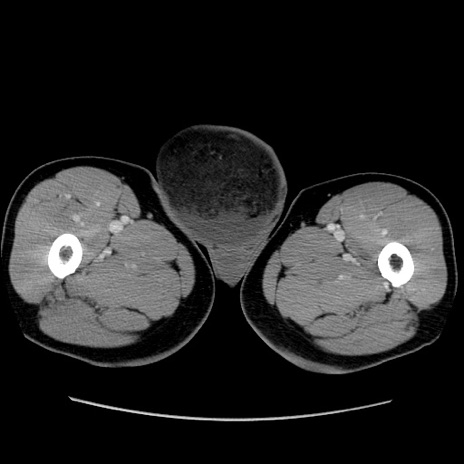

症例34(横断像)

【症例】60歳代 男性

【主訴】右鼠径部膨隆

【現病歴】1年程前より右鼠径部膨隆あり。自己にて還納可能だったため放置していた。3時間前より右鼠径部の脱出を認め、還納困難となり受診。

【既往歴】高血圧

【身体所見】右鼠径部に小児頭大の膨隆あり。弾性硬であり、用手還納は困難。左鼠径部にも膨隆を認める。脱出はなし。

【データ】WBC 15500、CRP 測定なし